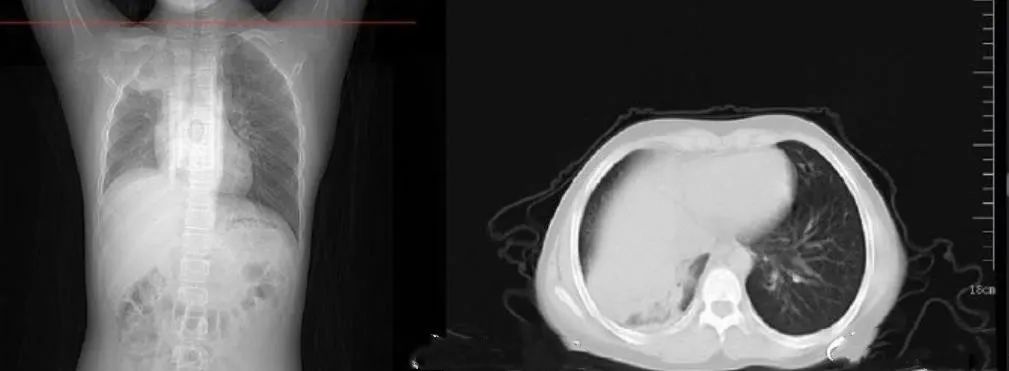

武汉12岁男孩周周,感染新冠病毒后,被查出白肺。

白肺,是肺部影像学表现的一种口语化描述,也是这波大感染中,令我们很多人谈虎色变的重症。

儿科大夫给周周检查后,发现孩子一侧肺部组织已经大面积变白,发展成了严重肺炎。

毕竟,重症白肺的死亡率,高达40%以上。